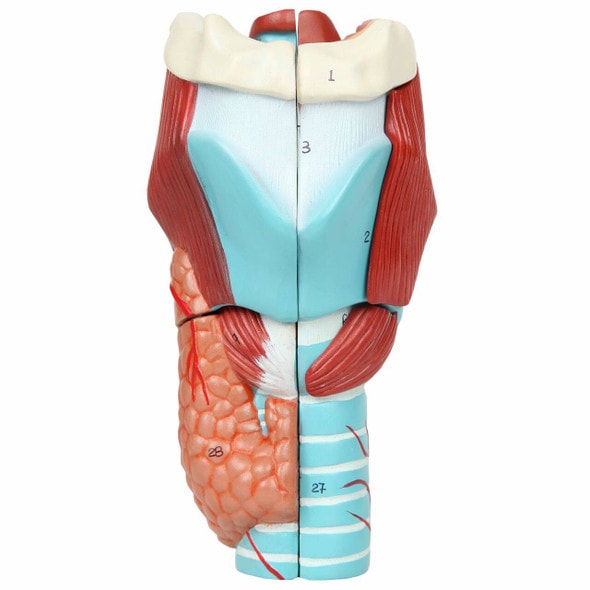

Anatomically Accurate Enlarged Human Throat Model Uganda Comprehensive Shopping Experience More professional XINDAM anatomical model was developed with the support of anatomical experts. The cat enclosure features a front door at a height of 71" with latchs, making it convenient for adult humans to access and with their feline Human Anatomy Model STZJBD Human Anatomical Nasal Cavity Throat Anatomy Medical Model For Science Classroom Study Display Teaching Medical Model(Color:A Brain Model Anatomy Anatomical Nasal Cavity Throat Anatomy Medical Model for patient education and anatomical study Buy Educational odel Huan Nasal Cavity Anatoy odel edical Nose... If you are a doctor, it is also an aid to patient education. 1.This model shows the internal structure of the mouth, nose, pharynx, and larynx as well as structures such as cerebrovascular and cranial nerves. (with digital mark) 2. This exceptional anatomical model offers a great view of the human nasal cavity throat. 3. Human life-size nasal cavity throat model mounted on a base for use in patient education or anatomical study. 4. Anatomical models are typically used as educational aids in medical and scientific classrooms and office settings. 5. Made of high quality PVC. 6. XINDAM provides an in-depth and cost-effective approach to anatomy research. Good teaching presentation learning resources tools. Is a good tool to help you learn anatomy. Professional Human Nasal Cavity Throat Model XINDAM Anatomical Model Human Nasal Cavity Throat Model was developed with the support of anatomical experts, vivid details, and gives you incredible visual insight into the intricate details of the human nasal cavity throat. This Anatomical nose larynx Nasal Cavity Throat model is made of polyvinyl chloride (PVC) plastic, which is corrosion resistant, lightweight, and has high strength. More focused, more professional.